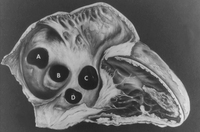

Subtipos de comunicaciones interauriculares: (A) seno venoso; (B) ostium secundum; (C) ostium primum; (D) seno coronario sin techo

Mayo Clinic Foundation